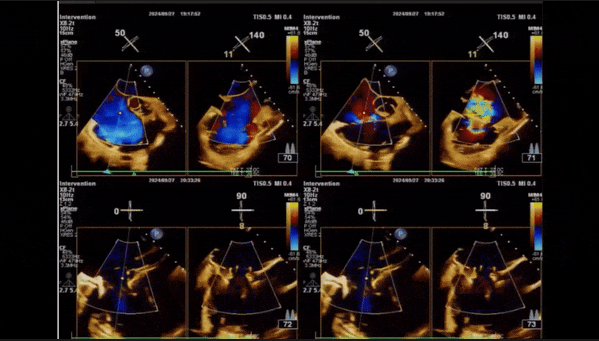

1、3D TEE顯示雙房及右室擴大,右室中段直徑40mm,右室FCA 52%。三尖瓣環TAPSE 22mm,三尖瓣環左右徑49mm,三尖瓣隔葉長度16mm,前葉長度21mm,后葉長度34mm,三尖瓣前隔gap 11mm,后隔gap 5.6mm,AP gap 12mm,診斷極重度功能性三尖瓣返流(Type I型三尖瓣:Torrential FTR 5+)。

2、彩色多普勒顯示:收縮期三尖瓣口返流束起源于后隔交界、前后葉之間及前隔交界,返流束縮流頸最大寬度27mm,三尖瓣返流口EOA=2.02cm2,返流容積124ml,收縮期三尖瓣返流峰值速度2.64m/s,返流峰值壓差28mmHg,PAPs 43mmHg,舒張期三尖瓣口平均跨瓣壓差1mmHg,肝左靜脈可見明顯逆向血流波。

術中經食道超聲輔助下可見LuX-Valve Plus夾持件抓捕瓣葉狀態良好,夾持件在位,室間隔錨定位置良好,假體瓣膜整體錨定狀態穩固。

術后三維超聲

術后即刻經食道超聲可見,三尖瓣假體瓣膜位置合適,牛心包瓣葉運動狀態良好,開閉正常,瓣周及瓣葉對合緣處未見明顯返流,心電圖及心包狀態較術前無明顯變化。

術前術后返流情況對比